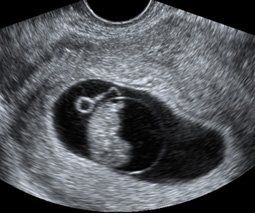

Early Pregnancy Scan

- Confirmation of an early/viable pregnancy

- Measurement of the gestation sac and the Crown Rump Length (CRL)(if possible)

- Detection of heartbeat. (If Pregnancy is more than 6 Weeks.

- Between 6 and 10 weeks.

- 2x b/w images.

- 30 minutes appointment.